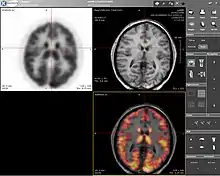

O TEP-IRM é a sigla de tomografia por emissão de positrões-imagem por ressonância magnética - em inglês: PET-MRI.

O TEP-IRM apareceu da reunião do exame imagiológico da medicina nuclear que utiliza radionuclídeos que emitem um positrão, no momento da sua desintegração, o qual é detectado para formar as imagens do exame, o TEP, e da IRM, a técnica que permite determinar propriedades de uma substância através do correlacionamento da energia absorvida contra a frequência, na faixa de megahertz (MHz) do espectromagnético, caracterizando-se como sendo uma espectroscopia [1].